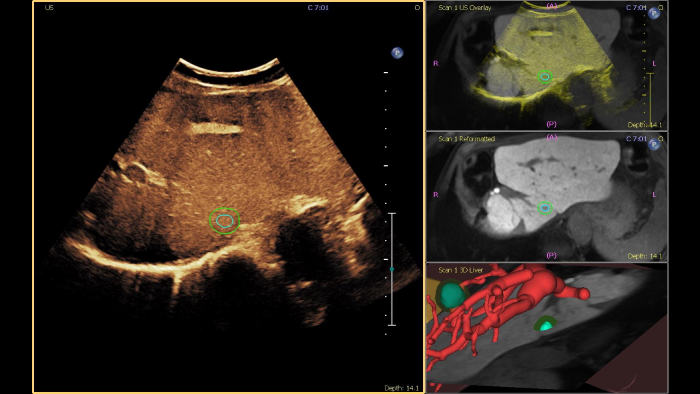

Philips ultrasound systems for interventional radiology support a range of sophisticated capabilities for interventional applications. Streamlined workflow allows clinicians to achieve fast and effective fusion of CT/MR/PET/CBCT with live ultrasound, while needle navigation aids in guiding biopsy and ablation of small and difficult-to-access lesions. Fusion and navigation can also be used in conjunction with Contrast-Enhanced Ultrasound (CEUS), giving clinicians access to even more powerful diagnostic tools with advanced visualization.

Achieve successful alignment of CT or MR volumes to ultrasound in <1 minute for the effective characterization of lesions. Registration of two imaging modalities by conventional methods can be time-consuming and technically challenging, often taking up to 10 minutes to achieve successful fusion.

This semi-automated tool helps outline a 3D contour around a structure of interest, improving procedure guidance even in challenging cases where the lesion may not be visually obvious under ultrasound. The lesion can be rendered in 3D or 2D via a complementary modality and overlaid on the live ultrasound or CT, helping visualize the location in relation to surrounding critical structures.

Offering the industry’s only interventional workflow with CT-only needle navigation on an ultrasound system, image fusion and needle navigation unlocks flexibility and opens up new possibilities by making image fusion and the use of ultrasound imaging completely optional. Needle location in relation to CT is tracked and updated in real time for procedural visualization, allowing providers to tackle complex cases and anatomy, even where ultrasound imaging is not possible. Continuous patient tracking technology. Once the registration step is complete, the patient can move, change position, and the field generator can be moved in or out of the procedure space without losing anatomical landmarks or diminishing tracking accuracy.